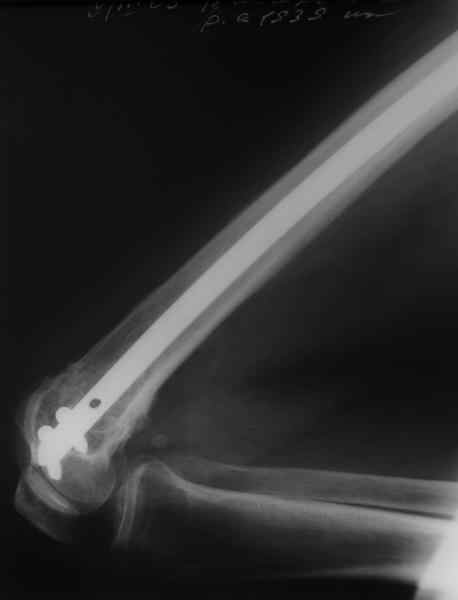

Чтобы больной не смог сгибать колено, выстоять в сустав железо должно побольше значительно, чем на 1 мм. В приложении снимок с выстоянием ммм на 3, видна и функция колена. Хотя клиника импинджмента была, но даже не на один восклицательный знак. После удаления стержня проблемы и вовсе рассосались.